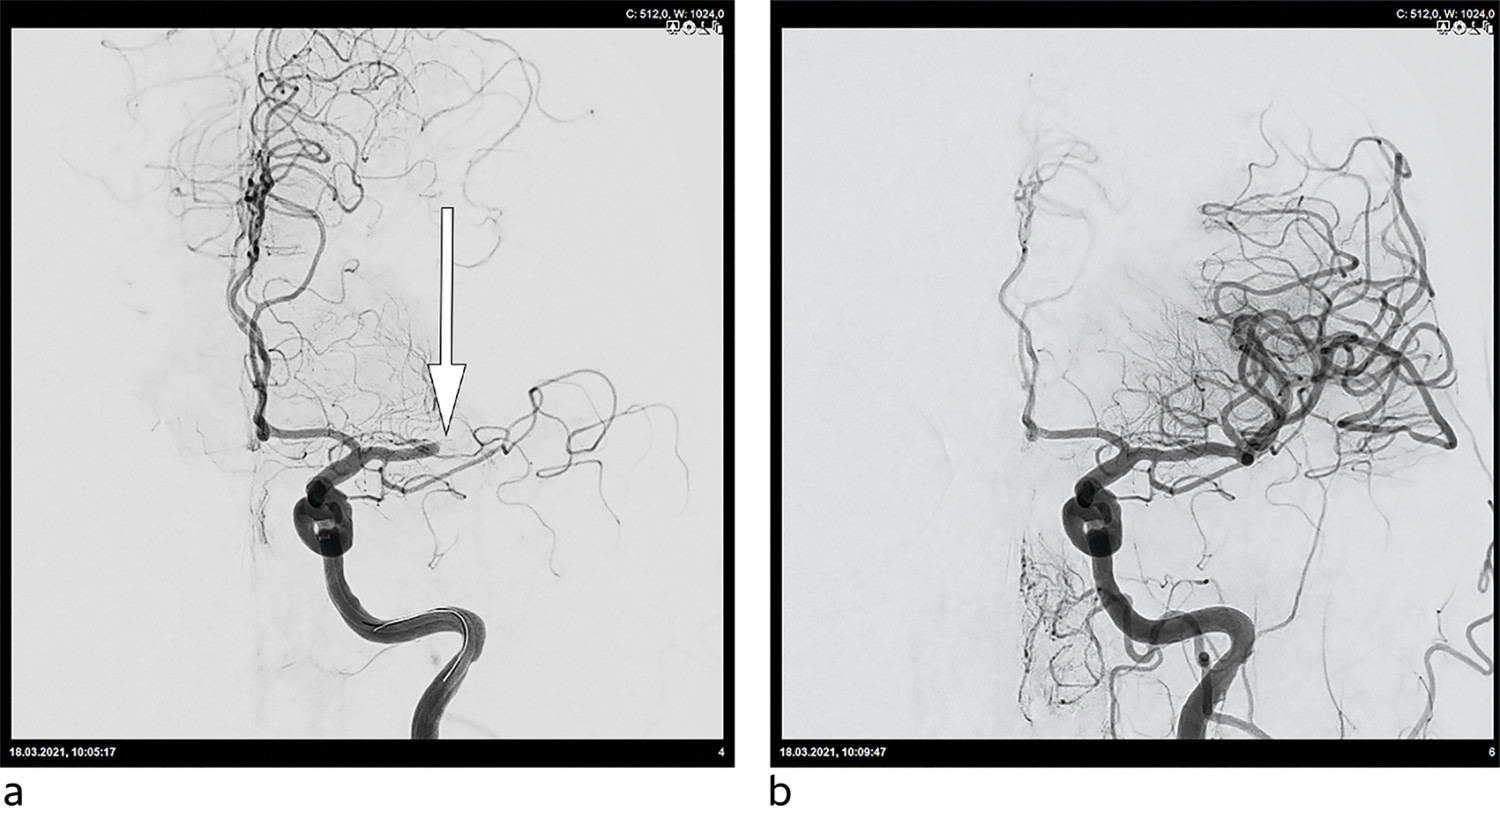

Tandemokklusjoner er spesielt utfordrende både teknisk sett og med tanke på en nødvendig bruk av antitrombotiske medikamenter for å holde stenten åpen. Pasientene vil som regel behandles med carotisstent kombinert med trombektomi (figur 3). Okklusjoner og stenoser i a. basilaris og a. cerebri media kan også ved indikasjon stentbehandles (22).